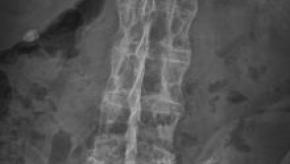

Gender Differences in Axial Spondyloarthritis

Rheumatic conditions such as SLE and RA exhibit female predominance. In contrast, increasing evidence suggests that gender differences occur in axial spondyloarthritis in terms of time to diagnosis, clinical manifestations, treatment outcomes and quality of life.

Identifying Gaps in axSpA: Lessons from European Map of Axial Spondyloarthritis (EMAS)

Despite the increasing scientific knowledge on axSpAs, a substantial gap still remains. Delay in diagnosis continues to pose a threat in the early identification of patients and those already on treatment may deal with additional issues such as work productivity or quality of life.